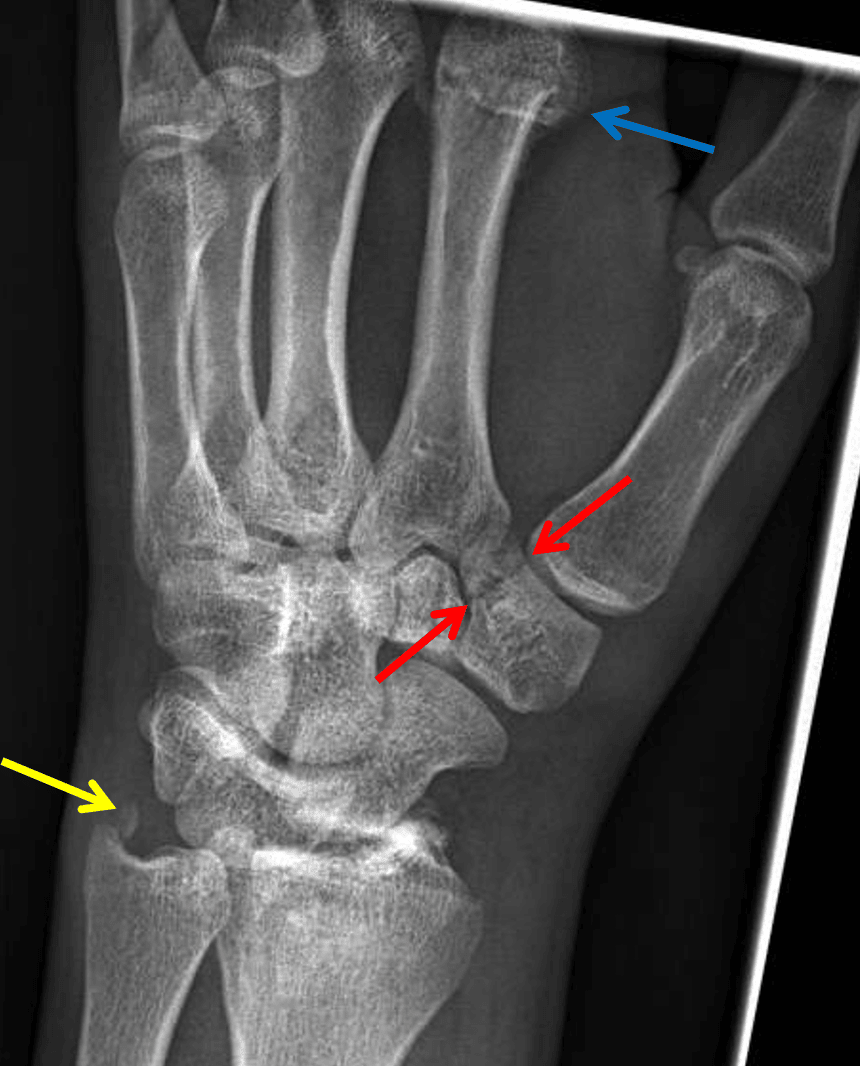

Red arrows: nondisplaced fracture of the trapezium. Yellow arrow: ulnar styloid fracture. Blue arrow: impacted second metacarpal neck fracture.